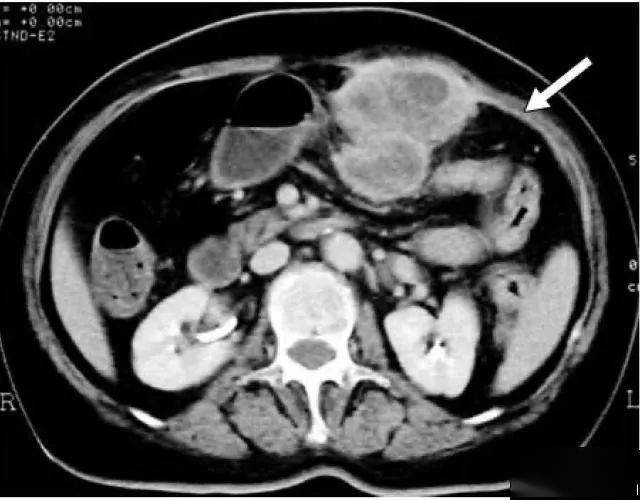

"网膜饼"(omental cake)是ct和mri成像上用来描述大网膜增厚的一个